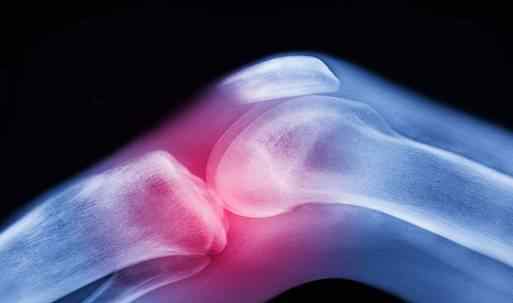

3.退化性变化

膝关节骨性关节炎多见于中老年女性,会出现骨质增生,俗称长“骨刺”。软骨退化脱落会产生游离体。当这些炎症因子刺激膝盖周围的软组织时,肌肉会突然痉挛,导致关节发软,部分活动关节会有摩擦音。严重的膝盖可能会出现内翻畸形和内侧疼痛。

半月板损伤是最常见的一种损伤。下肢负重,双脚固定,膝关节轻度屈曲,突然过度内旋或外旋,均可造成半月板撕裂。半月板损伤可引起明显的扁平化和软化,有时关节疼痛,活动受限,运动时弹跳。

膝关节慢性滑膜炎和外伤或过度劳损引起的滑膜皱襞异常肥大,也可引起“滑膜嵌顿”,即关节腔内漂浮的水草般的滑膜突然被挤压在关节之间,同时产生大量积液,使患者感觉膝关节软、痛、肿、嫩,甚至出现互锁症状,影响正常活动。